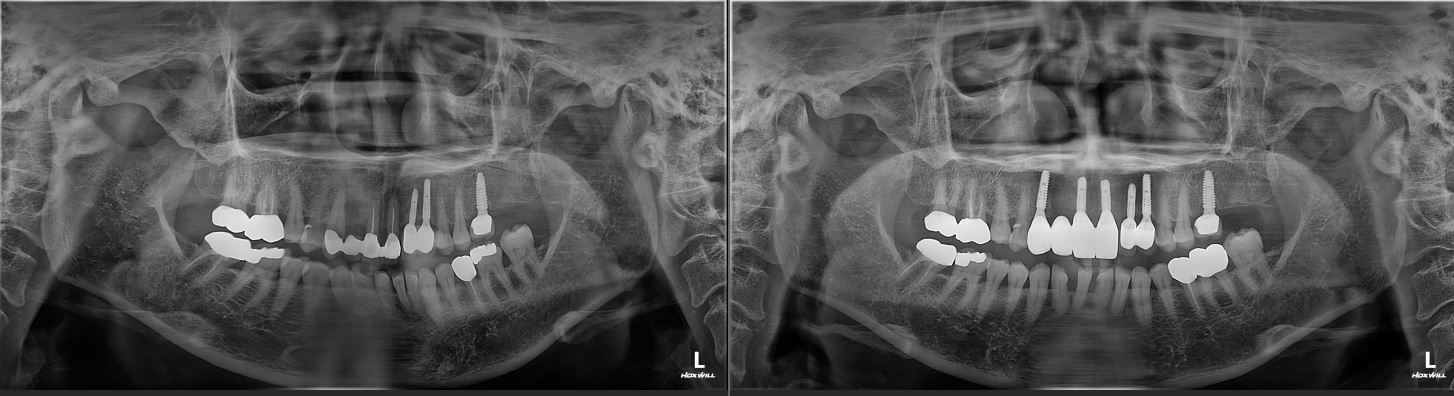

치료전후사진